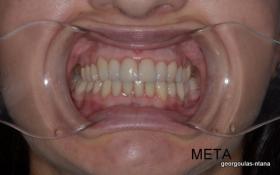

Η ασθενής ήταν δυσαρεστημένη με την αισθητική εμφάνιση των δοντιών της, κυρίως των άνω και κάτω πρόσθιων, τα οποία είχαν εκτεταμένες εμφράξεις σύνθετης ρητίνης που είχαν αποχρωματιστεί. Κάποια από τα οπίσθια δόντια έφεραν κακότεχνες προσθετικές αποκαταστάσεις (γέφυρα, στεφάνες) ενώ κάποια άλλα ήταν τερηδονισμένα. Η ασθενής επιθυμούσε το καλύτερο δυνατό αισθητικό αποτέλεσμα. Για το λόγο αυτό αποφασίστηκε να τοποθετηθούν μεμονωμένες ολοκεραμικές στεφάνες από διπυριτικό λίθιο (Emax) σε όλα τα δόντια της άνω και κάτω γνάθου, ώστε να εξασφαλιστεί το καλύτερο αισθητικό αποτέλεσμα. Χρησιμοποιήθηκε η τεχνική MIPP (Minimally Invasive Prosthetic Procedures) με ελάχιστη αποκοπή οδοντικών ιστών και μονολιθικές αποκαταστάσεις Emax στα οπίσθια δόντια.  Στη θέση του κάτω αριστερού πρώτου γομφίου, ο οποίος έλειπε και είχε αντικατασταθεί με γέφυρα που στηρίζονταν στα διπλανά δόντια, αποφασίστηκε να τοποθετηθεί εμφύτευμα. Σε όλη τη διάρκεια της θεραπείας η ασθενής ήταν καλυμμένη με προσωρινές προσθετικές αποκαταστάσεις.